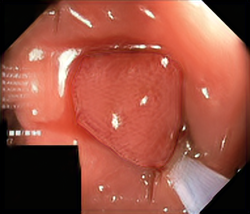

We have used a polyp dataset published with HyperKvasir dataset [51], which consists of polyp findings extracted from endoscopy examinations. HyperKvasir contains polyp images with corresponding segmentation masks annotated by medical experts. We use only this polyp dataset as a case study because of the time and resource-consuming training process of the SinGAN-Seg pipeline. However, the SinGAN-Seg model and pipeline can be used for any segmentation dataset.

A few sample images and the corresponding masks of the polyp dataset in HyperKvasir are shown in Fig 2. The polyp images are RGB images. The masks of the polyp images are single-channel images with white () for true pixels, which represent polyp regions, and black () for false pixels, which represent clean colon or background regions. In this dataset, there are different sizes of polyps. The distribution of polyp sizes as a percentage of the full image size is presented in the histogram plot in Fig 3, and we can observe that there are more relatively small polyps compared to larger polyps. Additionally, a subset of this dataset was used to prove that the performance of segmentation models trained with small datasets can be improved using our SinGAN-Seg pipeline, and the whole dataset was used to show the effect of using SinGAN-Seg generated synthetic images instead of a large dataset which has enough data to train segmentation models. In this regard, this dataset was used for two purposes:

After training SinGAN-Seg models, we generated random samples per real image using the input scale , which is the lowest scale that uses a random noise input instead of a re-scaled input image. For more details about these scaling numbers and corresponding output behaviors, please refer to the vanilla SinGAN paper [56]. Three randomly selected training images and the corresponding first synthetic images generated using scale are depicted in Fig 4. The first column of the figure represents the real images and the ground truth mask annotated from experts. The rest of the columns represent randomly generated synthetic images and the corresponding generated mask.